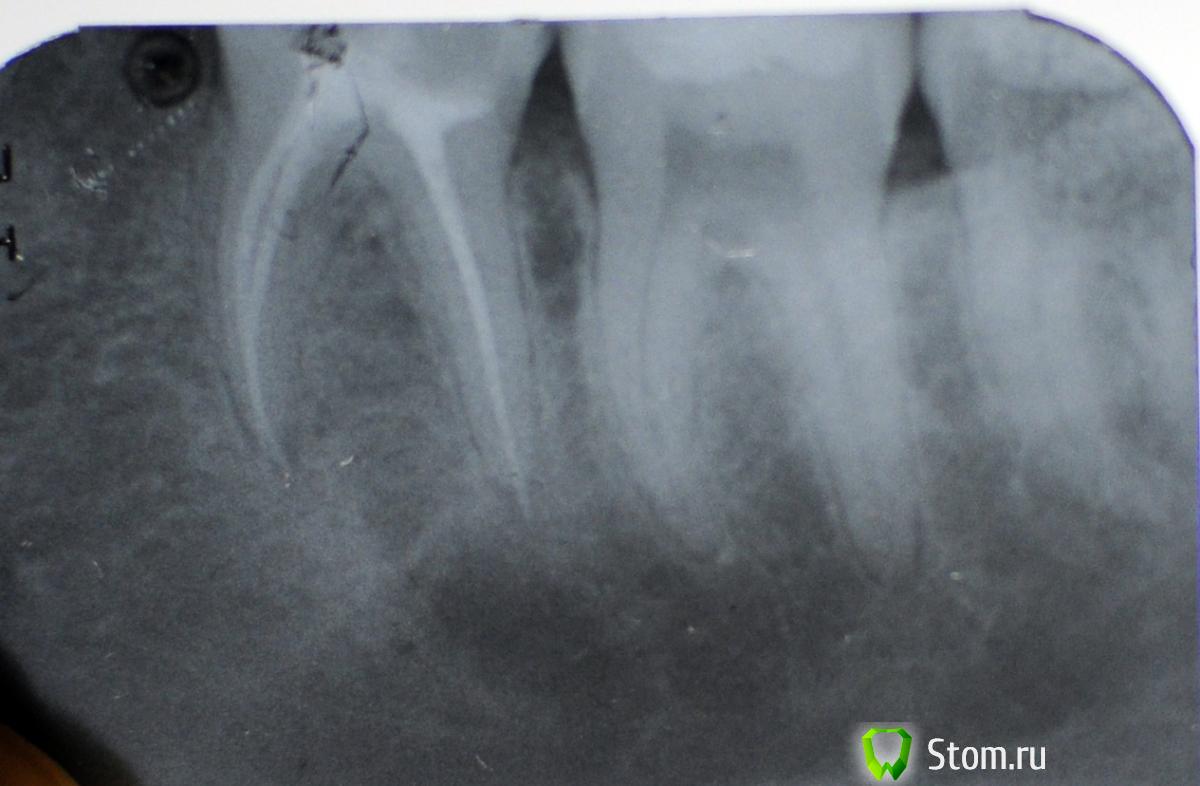

zadarom Опубликовано 8 апреля, 2012 Поделиться Опубликовано 8 апреля, 2012 Здравствуйте! 2 ноября 2011 года был депульпирован и запломбирован 36 зуб в государственной поликлинике. В течение следующих 2 месяцев зуб сильно ныл, было очень больно при смыкании зубов и накусывании, врач, лечившая зуб, сначала выписала линкомицин, затем через время электрофорез и лазер, на мое предложение сделать снимок ответила, что в этом нет необходимости. Результат лечения - нулевой. Боль не ушла и никак не изменилась, зуб так же сильно ныл днем и ночью. На холодное-горячее реакции не было. Я по своей инициативе сделала несколько снимков зуба в разных проекциях, на одном из них был четко виден пропущенный канал. Я обратилась в частную клинику, каналы распломбировали, пропущенный канал довели до ума, после лечения запломбировали снова (окончательно - 18 февраля этого года). 2 недели после этого зуб продолжал сильно ныть и болеть при смыкании зубов. 5 марта боль резко исчезла, но ровно через 20 дней, то есть 25 марта, резко появилась снова и продолжает мучить до сих пор. Сразу после повторного лечения на снимке было видно, что за верхушку выведен силер и примерно 1-2 мм гуттаперчи. На данный момент силера на снимке не видно, только выступающая за верхушку корня гуттаперча. Может ли этот злосчастный миллиметр гуттаперчи вызывать такую сильную ноющую боль? Показывала снимки нескольким стоматологам, мнения расходятся: одни говорят, что в выведении за верхушку ничего страшного нет и надо просто потерпеть, пока зуб успокоится, другие - что надо обязательно снова распломбировать каналы и все переделывать.Заранее спасибо. Ссылка на комментарий

zadarom Опубликовано 15 июня, 2012 Автор Поделиться Опубликовано 15 июня, 2012 Прошло почти 2 месяца после третьего перелечивания каналов. Зуб ноет нещадно, это нытье усиливается после еды. Все время хочется расшатывать зуб или нажимать на него сильно чем-нибудь твердым, тогда нытье уменьшается, а иногда резко прекращается на какое-то время. Сделала от безысходности компьютерную томограмму, может, на ней можно увидеть, что все-таки происходит с зубом? Ссылка на комментарий

zadarom Опубликовано 7 июля, 2012 Автор Поделиться Опубликовано 7 июля, 2012 Если кому интересно, 4 дня назад мне сделали реплантацию этого многострадального зуба. Зуб аккуратно расшатали и вырвали, из корней торчала гуттаперча длиной по 3-4 миллиметра, ее обрезали и вставили зуб на место, прикрепив к соседнему чем-то похожим на пломбу. Ничего не болит, отека нет, даже не было необходимости принимать обезболивающие. Зуб выглядит так, как будто с ним ничего не делали, и главное - сразу же ушла мучительная боль, изматывавшая меня последние 8 месяцев. И так вот бывает. Ссылка на комментарий